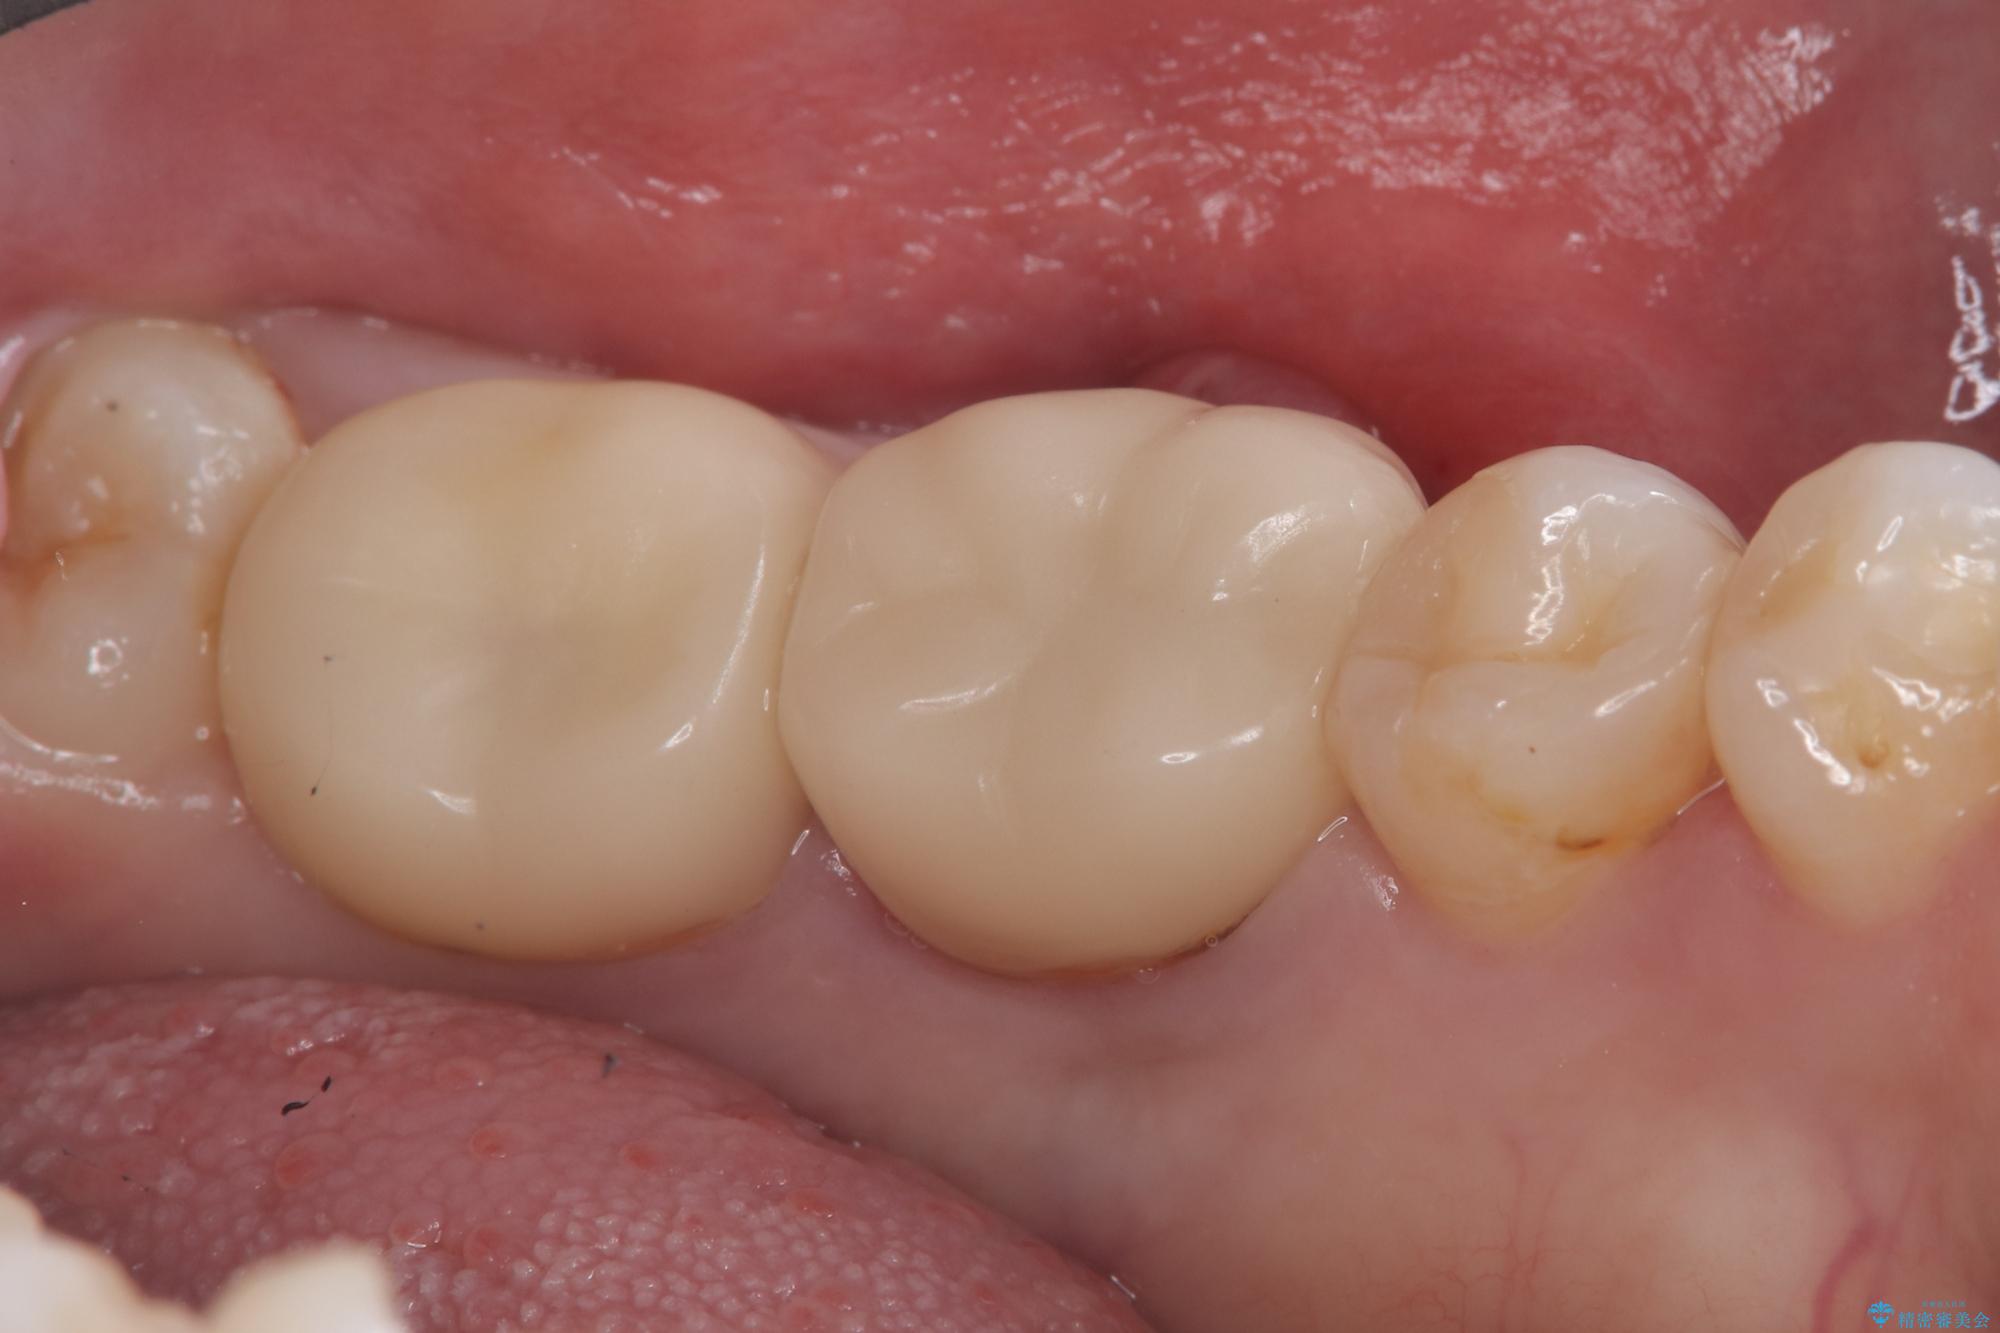

保存が難しい左下6番目の歯を抜歯し、左下8番目の歯(親知らず)を抜歯窩に移植しました。歯牙移植後の動揺防止のため暫間固定を行っています。

また移植後2週間経過時点で根管処置が必要となります。

骨との定着を確認し、今後矯正治療を行う予定のためレジン冠をセットしています。